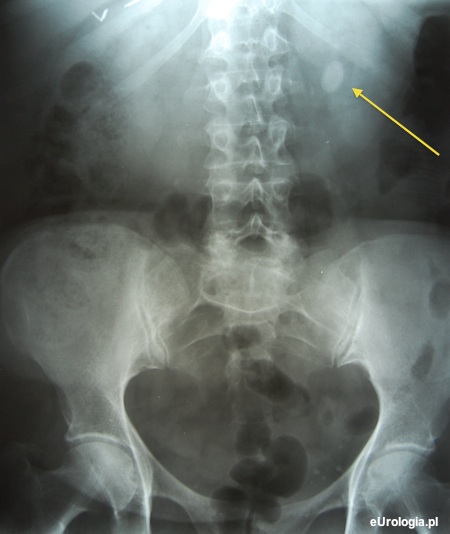

Zdjęcie przeglądowe jamy brzusznej w diagnostyce kamicy nerkowej

RTG przeglądowe jamy brzusznej w czasach, kiedy USG nie było dostępne było podstawowym badaniem we wstępnej diagnostyce kamicy nerkowej. Na zdjęciu rentgenowskim możliwe jest uwidocznienie zwapnień w rzucie układu moczowego, które mogą odpowiadać uwapnionym złogom w nerce. Blisko 75% złogów w nerce jest widocznych na zdjęciu rentgenowskim. Złogi zbudowane z kwasu moczowego są niewidoczne na zdjęciach RTG. Złogi cystynowe dają bardzo słaby cień na zdjęciach RTG lub są zupełnie niewidoczne. Zdjęcie przeglądowe jamy brzusznej nie powinno być wykonywane u kobiet w ciąży. Pacjentki w ciąży lub podejrzewające ciążę powinny poinformować o tym fakcie lekarza.

Fot. Zdjęcie przeglądowe jamy brzusznej z widocznym cieniem złogu długości 20 mm w obrębie miedniczki nerkowej.